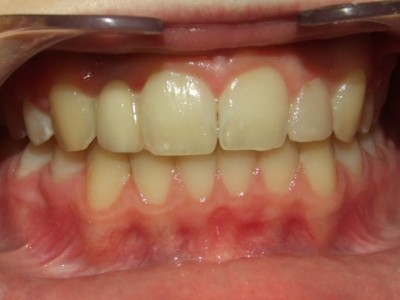

Voor behandeling

Na behandeling